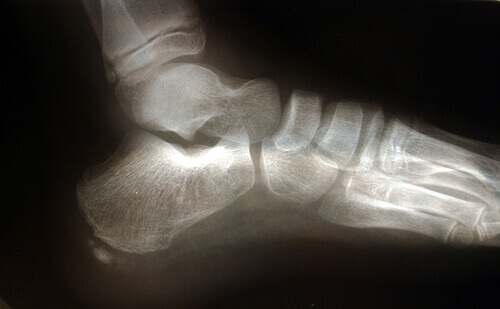

Анатомія ступні

Є кілька особливостей анатомічної структури нижніх кінцівок, які впливають на силу навантаження підошовного апоневрозу.

Ахіллесове сухожилля – це зв’язка, яка з’єднує литковий та камбалоподібний м’язи із п’ятою. Різке скорочення ахіллесового сухожилля призводить до збільшення тиску на п’яту та підошовний апоневроз.

Інша важлива особливість анатомічної структури ступні – це характер доторкання ноги до земної поверхні при ходьбі. Люди, які страждають на плоскостопість або викривлення ступні під час руху змушують апоневроз більше напружуватися. Оскільки сила тиску на сполучну тканину збільшується, ризик травмування та розриву апоневрозу зростає у кілька разів.

Плантарний фасциїт часто асоціюють з наявністю кісткової шпори у ступні, проте цей фактор не є головною причиною розвитку запального процесу.